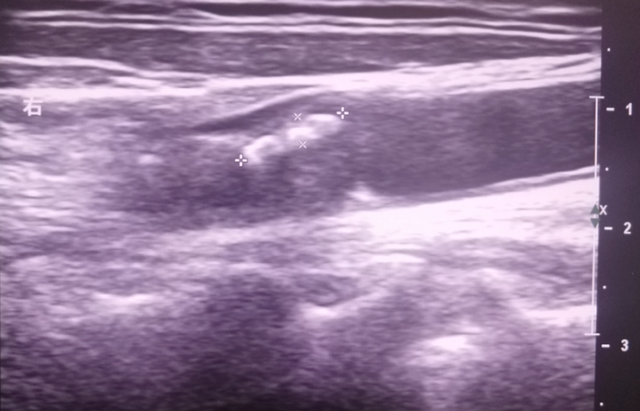

而颈动脉超声,就像一台“高清摄像头”,利用高频超声波无创、无辐射地探查这条生命线。它能清晰显示血管壁结构、血流情况以及有无斑块,为医生提供准确的诊断依据。

看斑块:不仅能测量斑块大小和狭窄程度,还能通过回声“识别”斑块是否危险——稳定斑块(强回声)像“厚皮饺子”,不易破裂;而不稳定斑块(低回声)则像“薄皮包子”,容易破裂引发脑梗。这种识别能力是很多检查难以替代的。

看血流:利用多普勒技术测量血流速度。血管一旦狭窄,局部血流就会加速,通过速度变化不仅能精确判断狭窄程度,还能在头晕等症状出现前,就发现早期的血流异常,真正做到防患于未然。